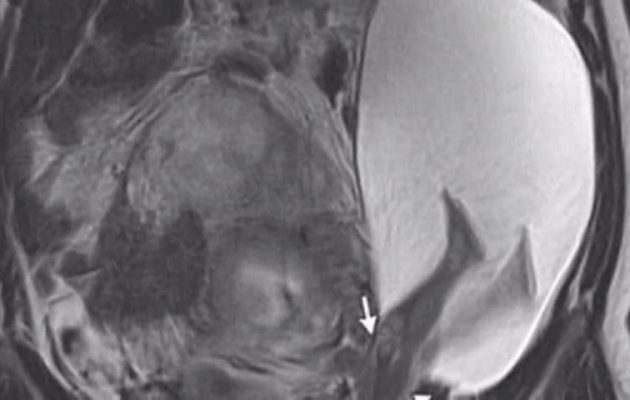

Ρήξη μήτρας από… δυνατή κλωτσιά του εμβρύου; Κι όμως συνέβη σε μία γυναίκα που ήταν έγκυος και η οποία τελικά γέννησε πρόωρα ένα υγιέστατο κοριτσάκι.

Η γυναίκα μεταφέρθηκε εσπευσμένα σε νοσοκομείο του Πεκίνου, αφού παραπονέθηκε για έντονους πόνους στην κοιλιακή της χώρα. Κάτι που έμελλε να αποδειχθεί πως ήταν… ρήξη μήτρας!

Ο Dr. Zhong Shilin, είναι ο γιατρός που έκανε την επέμβαση στη γυναίκα. Και δήλωσε πως η διάμετρος της οπής ήταν επτά εκατοστά.

Στο παρακάτω βίντεο σημειώνονται με κόκκινο κύκλο τα πόδια του εμβρύου που φαίνονται να έχουν διασπάσει τον «τοίχο» της μήτρας.

Ένα περιστατικό εξαιρετικά σπάνιο, αφού μόλις μερικές δεκάδες παρόμοια έχουν καταγραφεί παγκοσμίως.

Σημειώνεται πως η γυναίκα υπέστη πλήρη ρήξη μήτρας.

Αποτέλεσμα αυτής, είναι η αυτόματη ρήξη των υμένων.

Συνεπώς το έμβρυο είναι δυνατό να εξέλθει στην ελεύθερη περιτοναική κοιλότητα και να ακολουθήσει αποκόλληση του πλακούντα.

Ο τρόπος αντιμετώπισης της ρήξης είναι η άμεση εκτέλεση λαπαροτομίας, προκειμένου να σωθεί τόσο το έμβρυο όσο και η μητέρα, η οποία κινδυνεύει άμεσα από την ακατάσχετη αιμορραγία.